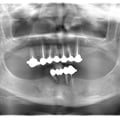

Залізна людина )))